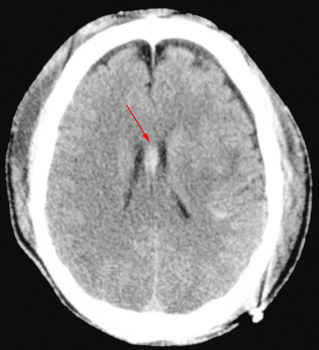

With CT, diffuse axonal injury may appear as ill-defined areas of high

density or hemorrhage in characteristic locations. The injury occurs in

a sequential pattern of locations based on the severity of the trauma.

The following list of diffuse axonal injury locations is ordered with

the most likely location listed first followed by successively less likely

locations:

- Subcortical white matter

- Posterior limb internal capsule

- Corpus callosum

- Dorsolateral midbrain